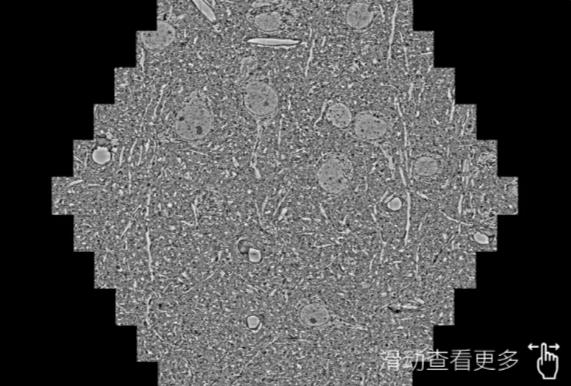

鼠脑切片。左图使用长宁蔡司长宁扫描电镜MultiSEM706对165μmx143pm面积区域成像,耗时仅需1.5秒。右图为鼠脑切片中30μm区域放大效果。样品由芝加哥大学B.Kasthuri提供。

使用蔡司高速长宁扫描电镜MultiSEM对1mm²人脑皮层组织进行高分辨成像,并对其中的各种细胞结构进行三维重构分析。左图展示了2x3mm²组织平面中锥体神经元的三维重构效果。右图显示了局部体积神经元三维重构。图像由哈佛大学chtman实验室提供,渲染图由D. Berger 制作。